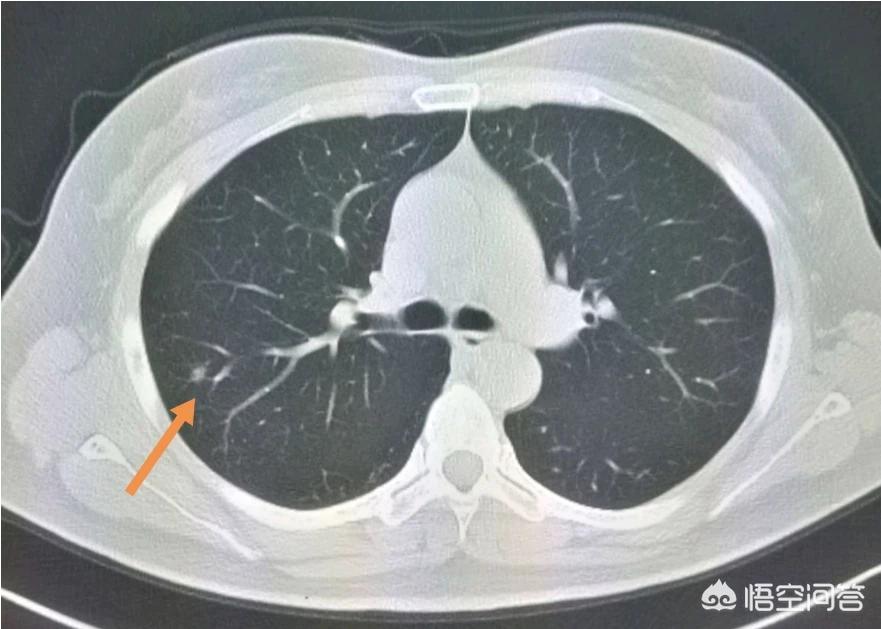

这是一位老烟民,咳嗽,痰里带血丝,CT发现右肺下叶后基底段支气管壁局部增厚,呈指套征,支气管镜证实为早期肺鳞癌